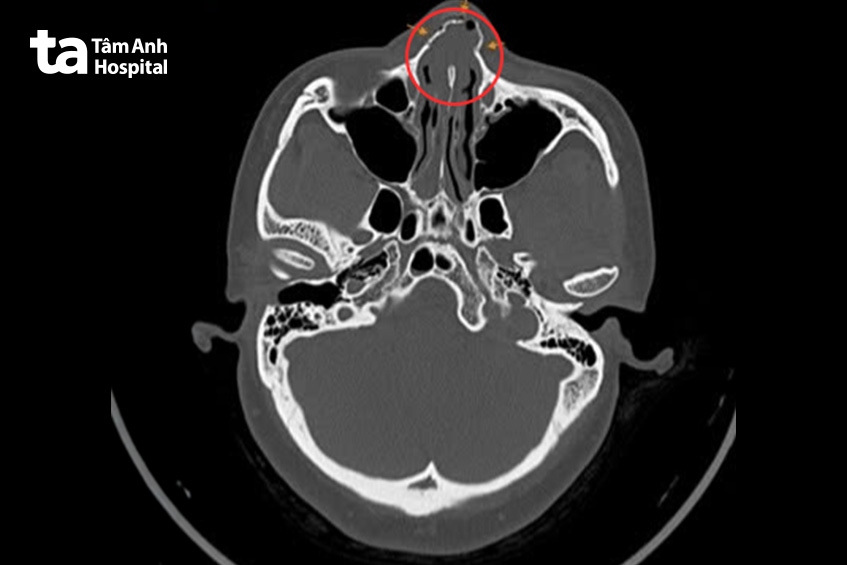

Kết quả chụp CT-scan vùng hàm mặt thấy xương mũi gãy kín thành nhiều mảnh, sưng nề phần mềm, vẹo vách ngăn mũi sang trái. Bác sĩ Trà Linh chẩn đoán chị Hàn vỡ xương chính mũi, chấn thương phần mềm vùng má bên trái, chấn thương răng, không thủng nhĩ. Trước đó, chị Hàn từng phẫu thuật thẩm mỹ nâng mũi, chỉnh sửa dáng mũi.